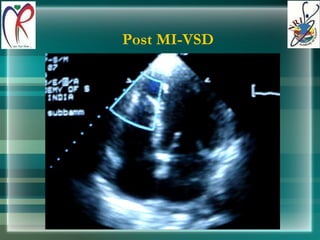

Post MI-VSD